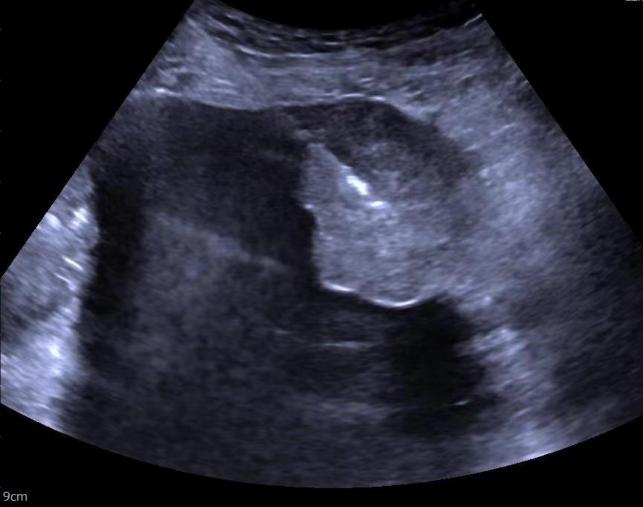

刘奶奶因腹膜后巨大占位多方求医未果,后至我院普外科入院,CT扫查显示为腹膜后巨大占位,部分液化。

穿刺活检进行病理学检查是肿瘤诊断的“金标准”。为精确诊断,超声医学科秦川主任对患者进行肿块穿刺活检,因肿块达20cm,为提高穿刺取材的准确性,秦川主任术前利用超声造影技术,以往传统穿刺可能因为术前未能定位肿瘤,需要多次穿刺,此次秦川主任术前利用的超声造影技术定位精准,精确导航肿瘤位置,一次穿刺成功,减少患者疼痛感,提高病理诊断准确性。此外超声造影对血管的显示优势明显,造影辅助,明显降低血管的损伤,减少术中出血量。术后刘奶奶无明显不适,无明显出血。